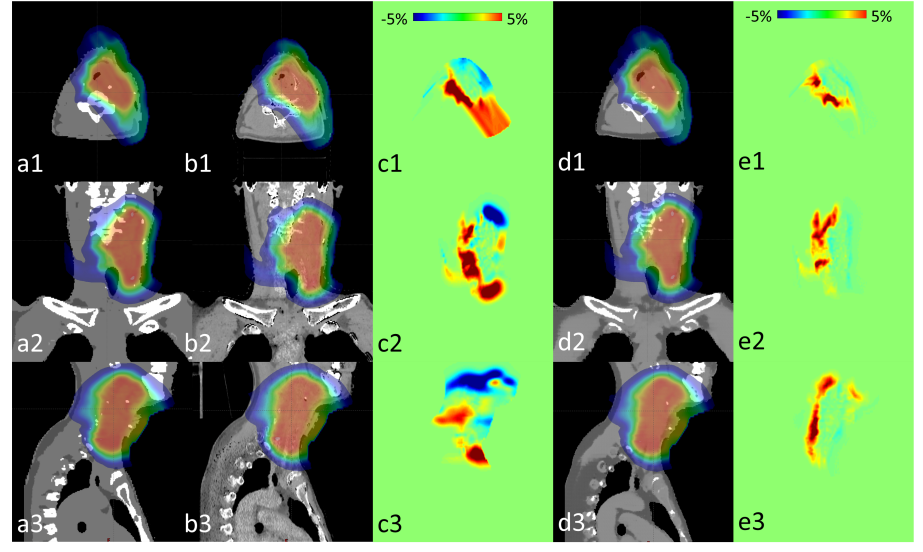

Fig. 6 compares the calculated proton dose maps at selected axial, sagittal and coronal planes of a patient as an example in the case of no additional noise simulated. The dose maps calculated on the ground truth qualitatively appear to be more similar on those of the predicted RSP maps by the proposed method than by the physics-based method. Most dose error of the proposed method is around the distal end of the beams, while that of the physics-based method happens at all the high dose-gradient regions to a much wider and severe extent.

Fig. 6. Dose distribution calculated on (a) ground truth, and predicted RSP by (b) physics-based method and (d) proposed method from DECT datasets of one patient without additional simulated noise presented in three orthogonal views (1), (2) and (3). The dose difference maps of (a) vs (b) and (a) vs (d) are shown in (c) and (e), respectively.